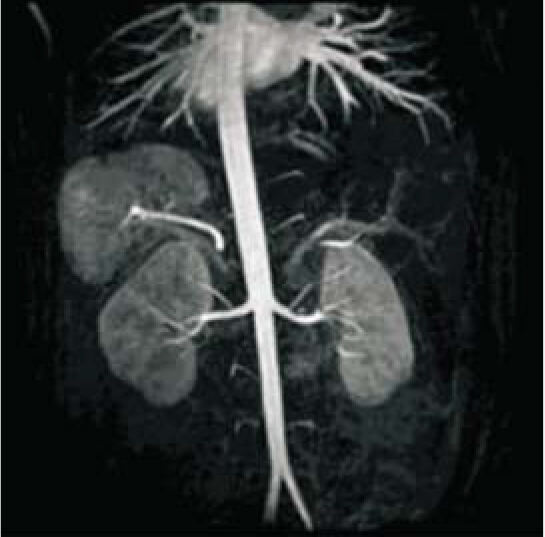

SuperMark 1.5T is a latest generation superconducting MRl system based on over 30 years of experience in research and development, which focuses on user's concerns. This system is equipped with a new upgraded hardware and software platforms with A-combi and Al technologies that benefit users a lot and deliver patients with more comfortable experiences. It features new user-friendly design, faster imaging speed, higher image quality and greatly improved work efficiency.

SuperMark 1.5T provides not only conventional pulse sequences and basic clinical applications, but also advanced functional applications. Moreover, it adopts brand new professional APEX operation system which ensures easy operation and fast diagnosis